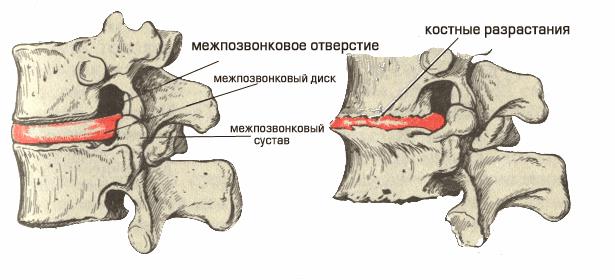

Механизм повреждения позвонков

При хроническом состоянии происходит постоянное, легкое, механическое раздражение нервного сплетения за счет измененного межпозвонкового диска или за счет костного разрастания, которое постоянно выпирает в позвоночный канал. Иногда стирается фиброзное кольцо межпозвонкового диска, из-за чего весь диск смещается назад.

Причина боли связана с ущемлением корешков спинномозговых нервов, например, из-за возрастных изменений костные новообразования тел позвонков могут уменьшить отверстие между ними. Причиной может быть также воспаление мышц или связок, расположенных вблизи нерва и давящих на его корешок.

При хроническом состоянии происходит постоянное, легкое, механическое раздражение нервного сплетения за счет измененного межпозвонкового диска или за счет костного разрастания, которое постоянно выпирает в позвоночный канал. Иногда стирается фиброзное кольцо межпозвонкового диска, из-за чего весь диск смещается назад.

При шейном спондилезе происходит разрастание клювовидных и шиповидных остеофитов по краям тел позвонков. Некоторые неправильно трактуют остеофиты как "отложение солей", но это определение неправильное, поскольку процесс развития остеофитов связан с костным перерождением связок. Чаще всего спондилез является следствием возрастных изменений (чаще в шейном отделе). С распространением профессий умственного труда число лиц, страдающих от боли в шее, боли в плече возросло.

Остеофиты, связанные с костным перерождением связок, являются главной причиной, из-за которой больные обращаются за медицинской помощью. На сегодняшний день многие специалисты с помощью мануальной терапии, массажа, лечебной физкультуры, хирургическим путем пытаются «разбить» эти костные разрастания, или хотя бы уменьшить их прогрессирование. К сожалению, эти воздействия малоэффективны.